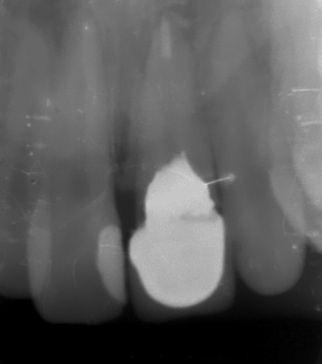

Chronic periodontitis of the 21st tooth (Photo 1 and 2).

The examination found a sinus tract with an active inflammatory symptomatology. The endodontic treatment failed to give any positive results. There was made a decision to extirpate the 21st tooth along with simultaneous placement of Alpha Dent Implant with its diameter of 5 mm, 13 mm long and closure of soft tissue defects with PRP membrane. The surgery was carried out without immobilization of mucosa-periosteal graft making it possible to attain a good aesthetic look of the gingival edge and harmonious “rose-and-white” ratio.